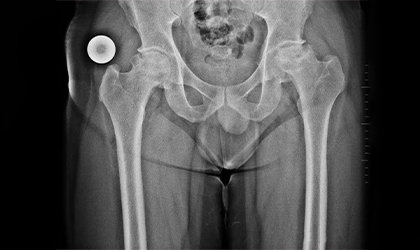

Imaging showed advanced avascular necrosis and collapse in both hip joints. A decision was made to proceed with bilateral total hip replacement during the same hospital stay.

This 34 year old medical representative had avascular necrosis with collapse of both her hips We replaced both his hips together. He was in hospital for 5 days. Presently symptom free